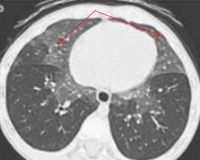

- Рентгенография сустава. При псориатическом артрите обнаруживают эрозии на краях суставных поверхностей, сужение суставной щели, остеопороз эпифизов и метафизов. При длительном течении заболевания определяют разноосевые смещения костей – так называемый «анархический» тип деформации, костные анкилозы, уплотнение периартикулярных тканей.

- КТ суставов. Компьютерная томография назначается для ранней диагностики заболевания, поскольку она показывает первые признаки артрита примерно за 12 месяцев до появления изменений на рентгенограммах. С учетом локализации болей проводят КТ кисти, позвоночника, колена и других суставов. Для уточнения состояния окружающих мягких тканей назначается МРТ.